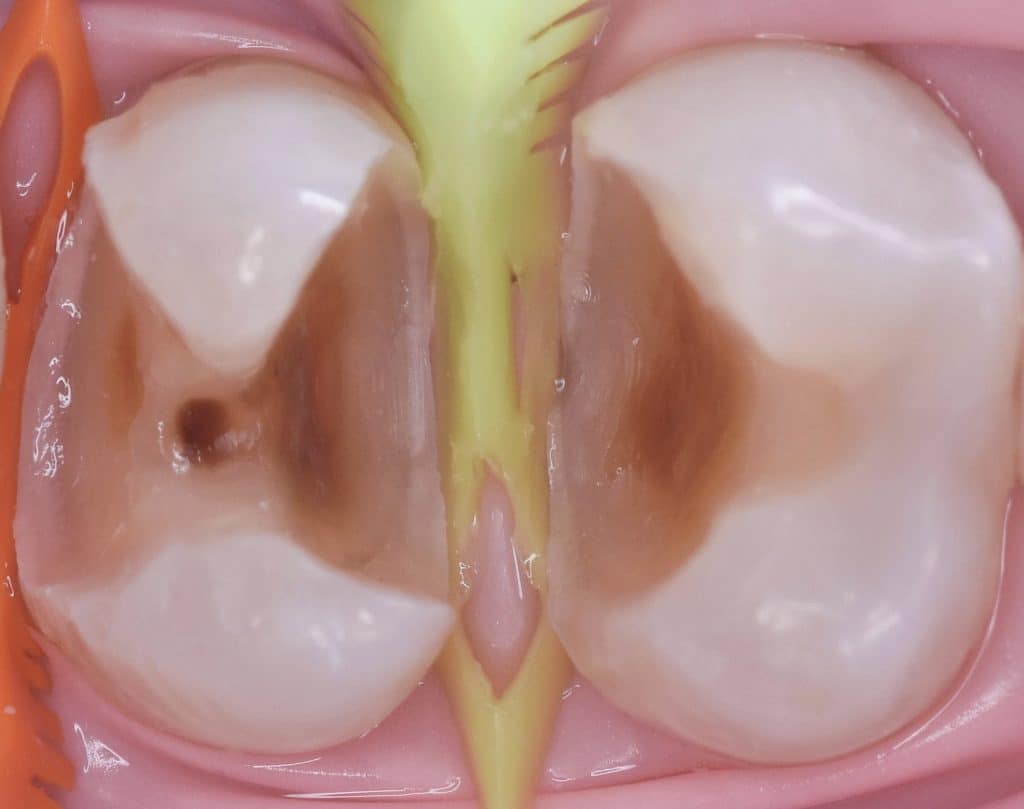

Rubber dam in place

Cavity design

Wedge selection

Caries removal end point

Start with first premolar

Place two mtarix back to back to equally divide the space